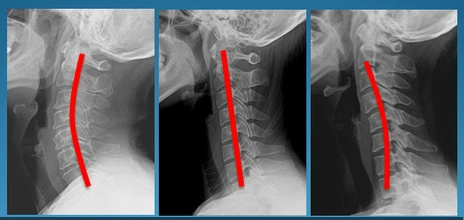

정상목 일자목 거북목

쉽게 말하자면 목의 모양은 알파벳 c의 형상을

띄어야 올바른 자세입니다. 그런데 일자형이거나

역 커브형으로 변형된 목이라면 거북목이라고 부르는데요